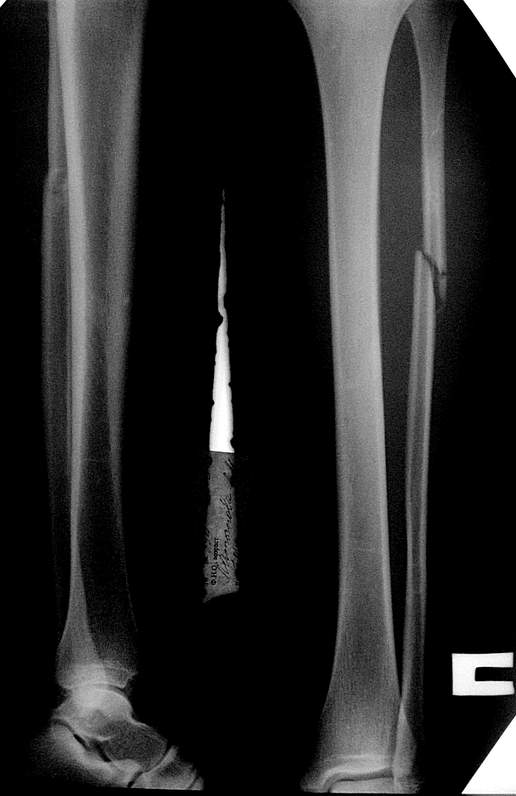

Проблема здесь не в переломе м/берцовой кости.

У больной есть боли в г/стопном суставе, возможно механизм травмы не прямой, тогда данное повреждение надо рассценивать как надсиндесмозное повреждение м\берцовой кости, пусть и такое высокое при Дюпиетреновском механизме травмы.

здесь пропускаем повреждение Maisonneuve...

Здесь как раз тот случай, когда рентгеновский снимок скрывает главную проблему. "Ходит, прихрамывая на правую ногу, отмечает боли в правом голеностопном суставе" По описанию клиника типичная для повреждения голонестопного сустава - синдесмоза.

При проксимальных переломах малоберцовой автоматически необходимо подозревать повреждение синдесмоза - Maisonneuve Fracture.

Описанное в 1840 году Maisonneuve повреждение характеризуется тем, что при фиксированной наружной ротации стопы повреждается передняя фибуло-тибиальная связка, часть синдесмоза, с переломом медиальной лодыжки и без, дальше разрыв продолжается по межкостной мембране и спиральный или косой перелом малоберцовой происходит выше.